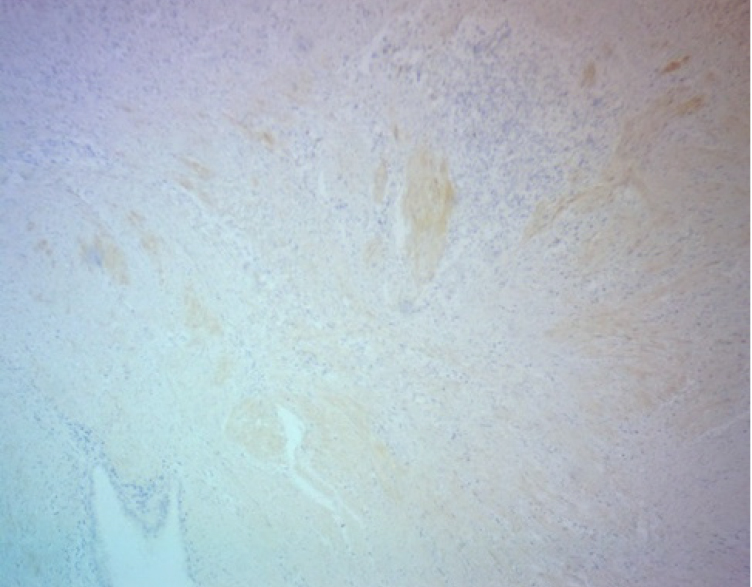

В цитогенной строме эндометриоидных гетеротопий и в соединительно тканных пролифератах была обнаружена положительная экспрессия трансформирующего фактора роста β-1. Площадь его экспрессии варьировала в разных наблюдениях от 10 до 15 % для цитогенной стромы и от 15 до 25 % для перифокально расположенных полей соединительной ткани (рис. 5).

Активная миграция клеток лимфо-макрофагального ряда, миофибробластов в очаг воспаления способствует секреции различных факторов роста, которые, в свою очередь, являются стимулами для запуска каскада реакций и развития фиброза как ответной реакции организма на повреждение тканей. Фиброз в данном случае направлен на отграничение от окружающих тканей очага эндометриоза, его инкапсулирование с целью предупреждения прогрессирования заболевания. Одним из главных индукторов фиброза является TGF-β1, который в высоких титрах определяется у женщин в перитонеальной жидкости, сыворотке крови, брюшине и в эутопическом эндометрии [3]. TGF-β1 продуцируется преимущественно макрофагами, эндотелиальными клетками и тромбоцитами и осуществляет при этом процессы регуляции клеточной пролиферации и дифференцировки, участвует в ангиогенезе, оказывает влияние на иммунный ответ [4, 5].

Миофибробласты представляют собой активированные повреждением клетки, основная функция которых заключается в регенерации внеклеточного матрикса [3]. Активацию миофибробластов связывают с действием TGF-β1 на фибробласты, что приводит к экспрессии α-SMA, который в настоящее время является основным маркером миофибробластов [6]. Кроме того, клетками-предшественниками миофибробластов могут являться мезотелиальные клетки брюшины, которые претерпевают мезотелиально-мезенхимальный переход под действием TGF-β1. В результате активированные клетки приобретают способность к миграции и накоплению коллагеновых волокон, то есть способствуют фиброзу [7].